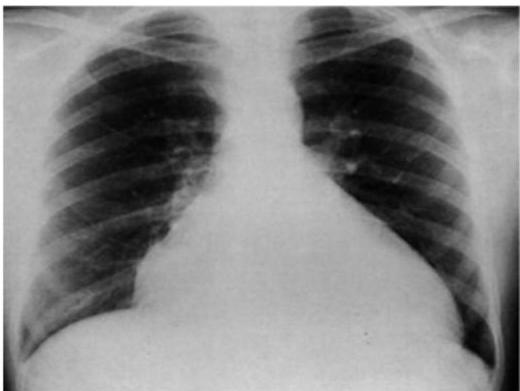

Asthma with Pneumothorax / Emphysema (CXR)

in This PIC Be Curfiat → Check Countage of the lung

Hint: Loss of contour of lung

- Check if hyperinflated

The hint is loss of Couture of lung in the emphysema → we doubt see?

Scenario: 5 year old with 3 days of acute asthma, progressive SOB, cyanosis.

CXR findings?

- Right-sided pneumothorax (or horizontal pneumothorax), subcutaneous emphysema, with left mediastinal shift

- Loss of lung opacity

- Mucous plug causing collapse/obstruction

- Other mentions in original: “Liver & mucus”, “Pneumonitis”

Examination Findings (Chest):

- Hyperresonance (increased sound on percussion)

- Pulsus paradoxus

- Decreased breath sounds

Management?

- Address the underlying cause (e.g., decompression for pneumothorax, airway clearance)

- Bronchodilator, inhaled steroid

- Suction + physiotherapy

- If pneumothorax: chest tube — 5th intercostal space, anterior axillary line

- Possible intubation